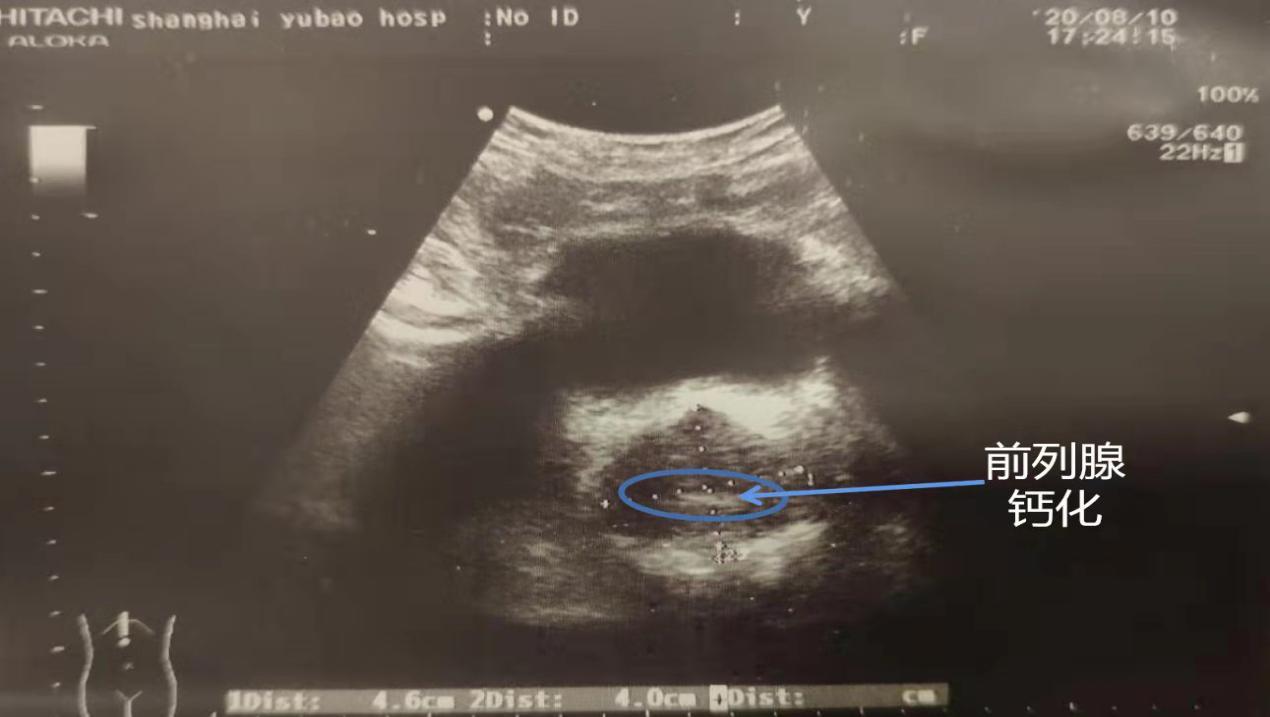

因缺乏典型的临床症状和体征,前列腺钙化多在检查前列腺疾病、泌尿系统其他疾病和常规健康体检时,经影像学检查被发现。在影像学检查中,前列腺钙化表现为前列腺内强回声灶或高密度灶,随着超声技术的普及与提高,前列腺钙化的检出率显著增加。

病灶点定位方法(b超加理疗棒法):做腹部b超,理疗棒插入肛门,在b超屏幕上可同时能看到理疗棒和钙化点(或回声不均匀的点(堵塞),或无回声点(囊肿)),这些点就是病灶点,移动理疗棒,让病灶点和理疗棒重合,用理疗棒反复顶病灶点,观察病灶点是否随着棒子动,最后记住这个位置的深度(用记号笔在理疗棒上标记)和角度(记住理疗棒偏几点钟方向),有的患者不止一个病灶点,需要依次定位,理疗时只做这些病灶点就行,有的患者担心出口堵塞,可以理疗一下中央沟位置。